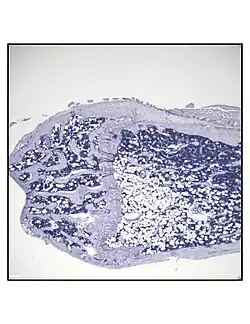

_.jpg) Representative distal femur histologic section of a 16-week-old healthy C57BL/6 mouse demonstrating a typical quantity of marrow adipocytes. Representative distal femur histologic section of a 16-week-old healthy C57BL/6 mouse demonstrating a typical quantity of marrow adipocytes.

Representative distal femur histologic section of a 16-week-old C57BL/6 mouse after 6 weeks of calorie restriction demonstrating an increased quantity of marrow adipocytes. Representative distal femur histologic section of a 16-week-old C57BL/6 mouse after 6 weeks of calorie restriction demonstrating an increased quantity of marrow adipocytes.